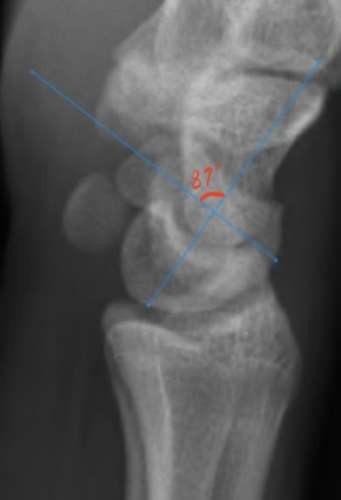

A 35-year-old woman reports wrist pain after a fall onto an outstretched hand. On exam, she has focal tenderness over the wrist snuffbox. A radiograph and CT image are shown in Figures A and B. What is the proper treatment of her injury?